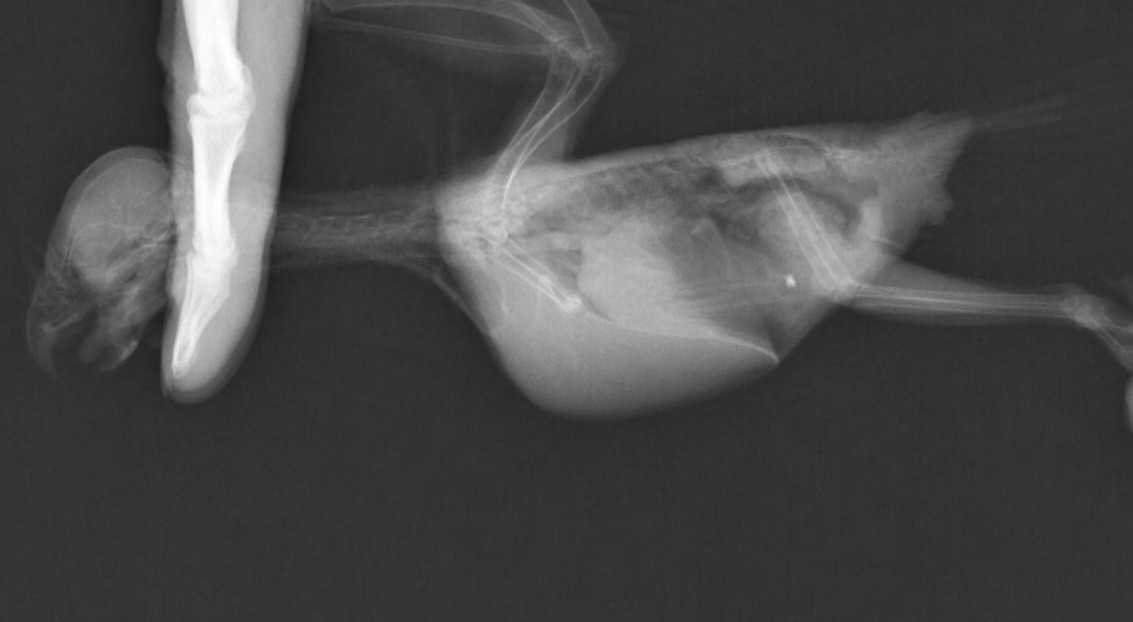

症例:2か月例 性別不明 オカメインコ

今朝から呼吸がおかしいとの主訴で来院。来院時、努力性呼吸で酸素化を行ったが短時間で亡くなってしまいました。

原因の究明のため検案を行いまして、左の肺の主気管支に膿がたまっておりまして、それが死因であるとしました。

膿瘍の大きさは1㎝にも満たない大きさでした。こんな小さなものでここまで重篤な症状が出てしまいます。鳥を飼育の方に置かれましては毎日の体重測定と呼吸状態の確認をお願いしております。